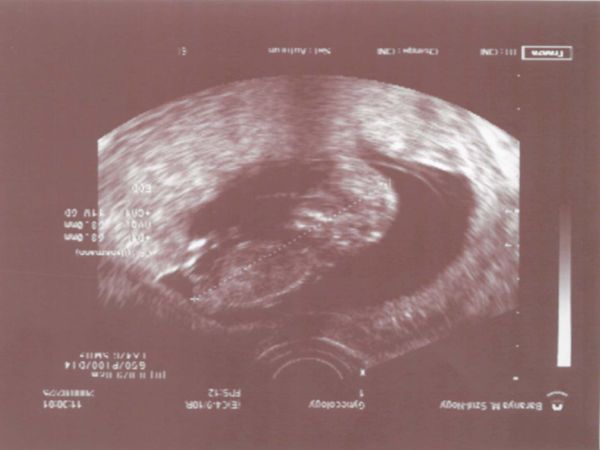

Mikor menjünk uh-ra? Hét vége felé jó lenne neked? hadd legyenek minél nagyobbak a csöppök...